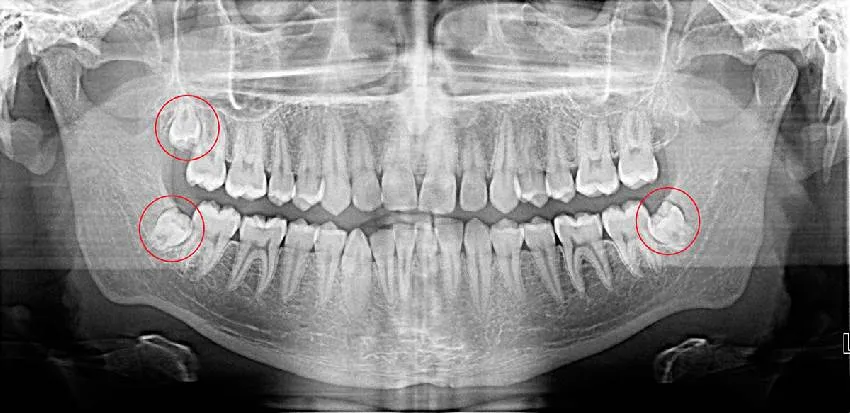

Для принятия решения о необходимости извлечения третьих моляров следует проконсультироваться с хирургом и ортодонтом, основываясь на панорамном снимке ОПТГ и, при необходимости, на результатах КТ (КЛКТ). Консолидированное мнение этих специалистов поможет определить, стоит ли удалять зачатки зубов мудрости.

Для чего и как удаляют зачатки зубов мудрости? Часто возникают проблемы с зубами, связанные с недоразвитием, когда зубы не могут прорезаться полностью из-за нехватки места. Это может привести к боли, повреждению корней и другим осложнениям. В такой ситуации зубы мудрости настоятельно рекомендуется удалить. Однако даже при использовании всех современных методов диагностики операция по экстренному удалению третьих моляров является сложной для пациента и хирурга.

Перед удалением зачатков зубов мудрости нужно получить консультацию хирурга-стоматолога, так как каждый клинический случай уникален и требует индивидуального подхода. Иногда не стоит удалять третьи моляры. Например, если восьмому зубу достаточно места, и он нормально растет. Также важно учитывать отсутствие вторых моляров, что может повлиять на правильное прорезывание восьмерок.

Перед началом ортодонтического лечения или во время активного прорезывания постоянных зубов выполняется панорамная ортопантомограмма. Этот вид визуализации позволяет взглянуть на все зачатки зубов на снимке, а также на молочные зубы, представляя полную картину зубного ряда и челюсти.